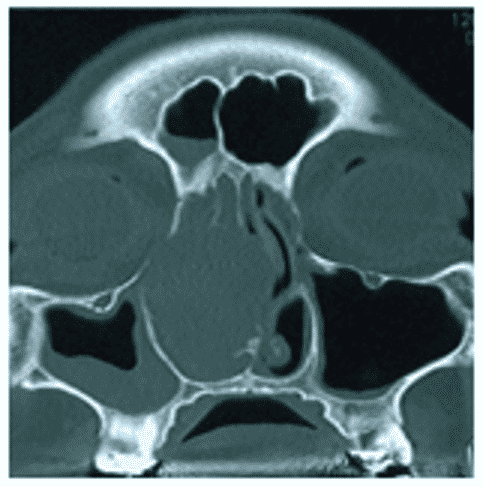

Фиброзная дисплазия на КТ характеризуется наличием относительно однородной, напоминающей матовое стекло, ткани плотностью, примерно, от 300 до 450 ед. Н, что ниже обычных денситометрических значений для спонгиозного слоя кости и соответствует плотности фиброзной ткани (рисунок 5).

Рис. 5. КТ околоносовых пазух, аксиальная плоскость. Фиброзная дисплазия верхнечелюстной (А), лобной (Б) пазух